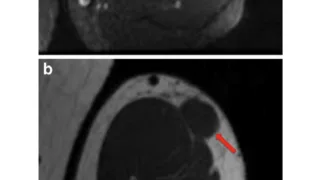

手術日+728日目 2026/2/25(水)(筋肉内神経鞘腫)